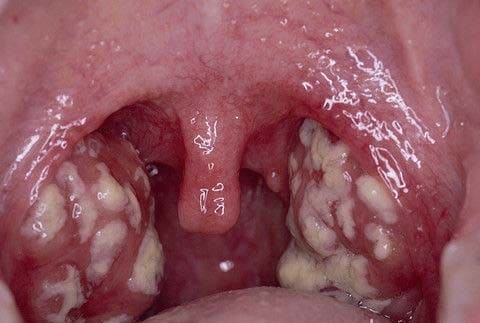

Ангина (тонзиллит) может быть как вирусной, так и бактериальной этиологии. Тонзиллит представляет собой воспалительный процесс в ротоглотке в области небных миндалин. Больных беспокоят боли в горле при глотании (исключение составляет дифтерия, когда боли незначительные), затруднение питья, приема пищи, температура, общая слабость. При осмотре слизистая ротоглотки гиперемированная (покрасневшая), небольшая отечность зева (исключение – дифтерия, при которой отек может быть значительным и является опасным симптомом в плане развития токсической формы болезни), миндалины увеличиваются в размерах до 1-3 степени в зависимости от выраженности процесса, на миндалинах появляются наложения. Если процесс катаральный, то рельеф миндалин сглажен и наложений нет, такая же картина при вирусной этиологии ангины. Если же это гнойная ангина, то наложения гнойного характера зеленовато-желтоватые, рыхлые, легко снимаются шпателем, располагаются в лакунах миндалин или по всех поверхности (исключение – дифтерия, при которой наложения серовато белые, плотные, тяжело снимаются шпателем, оставляя после себя кровоточащую поверхность). При грибковой процессе наложения на миндалинах имеют вид створоженного молока, белесовато-сероватый цвет, легко снимаются шпателем с поверхности увеличенных миндалин, чаще распространяются на небо, язык. При распространенном процессе наложения могут выходить за границы миндалин.

Вирусная ангина

Гнойная ангина

Дифтерия